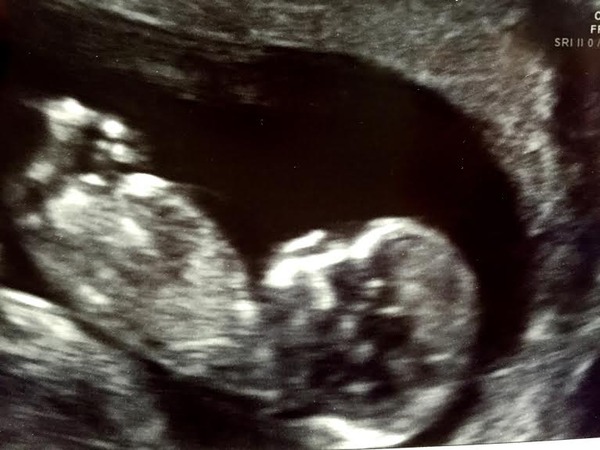

Hi everyone. All good news from my scan today. Showed a wriggly, healthy baby with all limbs intact! EDD is bang on for 16th June.

I have a little wriggler who didn't want measured today Grin all well, moved forward 3 dates so new EDD of 19/06/2016